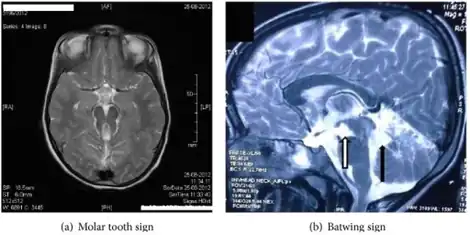

Detection of the hypoplasia of the cerebellar vermis is achieved through a cranial magnetic resonance imaging (MRI) scan. The presence of the ‘molar tooth sign’ (MTS) on the MRI scan, a mid- brain hind- brain malformation, confirms this condition and is a key indicator of COACH syndrome. The MTS's distinguished shape is attributed to the lengthened superior cerebellar peduncles and deepened interpeduncular fossa.[6] To diagnose ataxia, both neurological assessment and physical examination are required. This can include MRI scans, study of behavior and motor skills in infancy and analysis of family history and genetics. In the case of congenital ataxia, patients are born with the condition and thus diagnosis is more difficult, therefore diagnosis of ataxia alone is not sufficient to indicate COACH syndrome, and must be used in conjunction with other symptoms.[10] Oligophrenia, more commonly known as intellectual disability, is diagnosed using personalized testing to measure intelligence and physical examination for anomalies and facial dysmorphia.[14] Hepatic fibrosis has a range of diagnostic techniques, including invasive and non- invasive. Liver biopsy examination is an invasive technique, which uses liver tissue extracted from the patient to identify the degree and severity of the fibrosis, and may also provide insight on tumor growth. Ultrasonography- based tests use radiation waves to measure the stiffness of the tissue and are non- invasive. Serum tests are also non- invasive, and diagnose liver complications on the basis of the amount and presence of certain proteins and chemicals in the body.[15] Kidney cysts can be discovered using ultrasound techniques, and monitoring of the patient's urine concentrating ability for any abnormalities can indicate other renal complications such as nephronophthisis.[6][7]